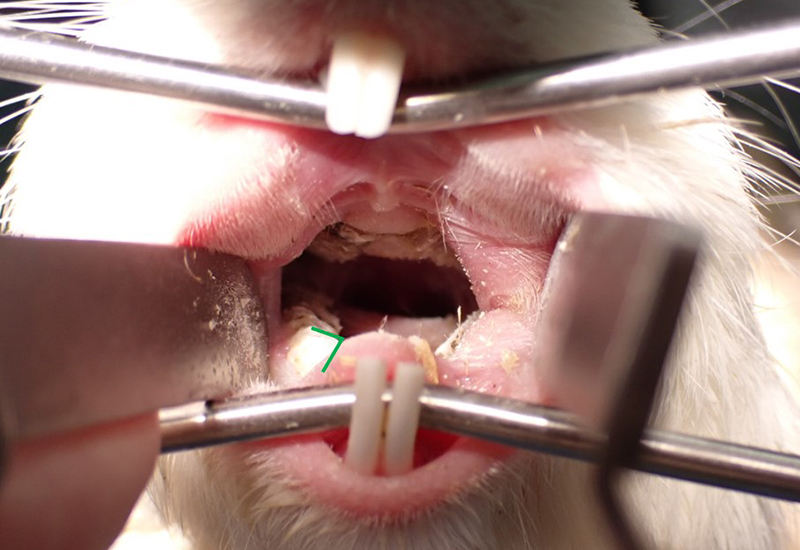

En esta ocasión, recortamos las muelas que habían crecido demasiado y también ajustamos ligeramente su ángulo.

boca de cobaya después del tratamientoEs un poco difícil de ver, pero ¿puedes notar que la parte que cubre su lengua se ha acortado? Además, el ángulo de sus dientes, que antes era plano, ahora está ligeramente inclinado. Me alivió verlo comer heno sin problemas después de despertar de la anestesia.